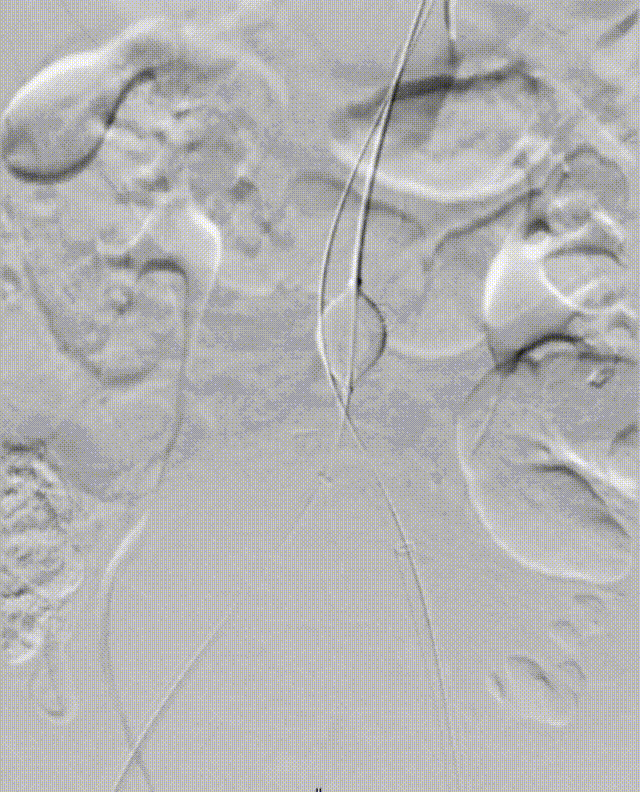

二、术前CTA详解

gore医疗怎么样「漫腹精论」髂合时宜 精益求精——双MOB球囊导管辅助腹主动脉覆膜支架急诊治疗破裂巨大髂动脉瘤_https://www.jmylbn.com_新闻资讯_第5张

gore医疗怎么样「漫腹精论」髂合时宜 精益求精——双MOB球囊导管辅助腹主动脉覆膜支架急诊治疗破裂巨大髂动脉瘤_https://www.jmylbn.com_新闻资讯_第6张

gore医疗怎么样「漫腹精论」髂合时宜 精益求精——双MOB球囊导管辅助腹主动脉覆膜支架急诊治疗破裂巨大髂动脉瘤_https://www.jmylbn.com_新闻资讯_第7张

gore医疗怎么样「漫腹精论」髂合时宜 精益求精——双MOB球囊导管辅助腹主动脉覆膜支架急诊治疗破裂巨大髂动脉瘤_https://www.jmylbn.com_新闻资讯_第8张

gore医疗怎么样「漫腹精论」髂合时宜 精益求精——双MOB球囊导管辅助腹主动脉覆膜支架急诊治疗破裂巨大髂动脉瘤_https://www.jmylbn.com_新闻资讯_第9张

gore医疗怎么样「漫腹精论」髂合时宜 精益求精——双MOB球囊导管辅助腹主动脉覆膜支架急诊治疗破裂巨大髂动脉瘤_https://www.jmylbn.com_新闻资讯_第10张

gore医疗怎么样「漫腹精论」髂合时宜 精益求精——双MOB球囊导管辅助腹主动脉覆膜支架急诊治疗破裂巨大髂动脉瘤_https://www.jmylbn.com_新闻资讯_第11张